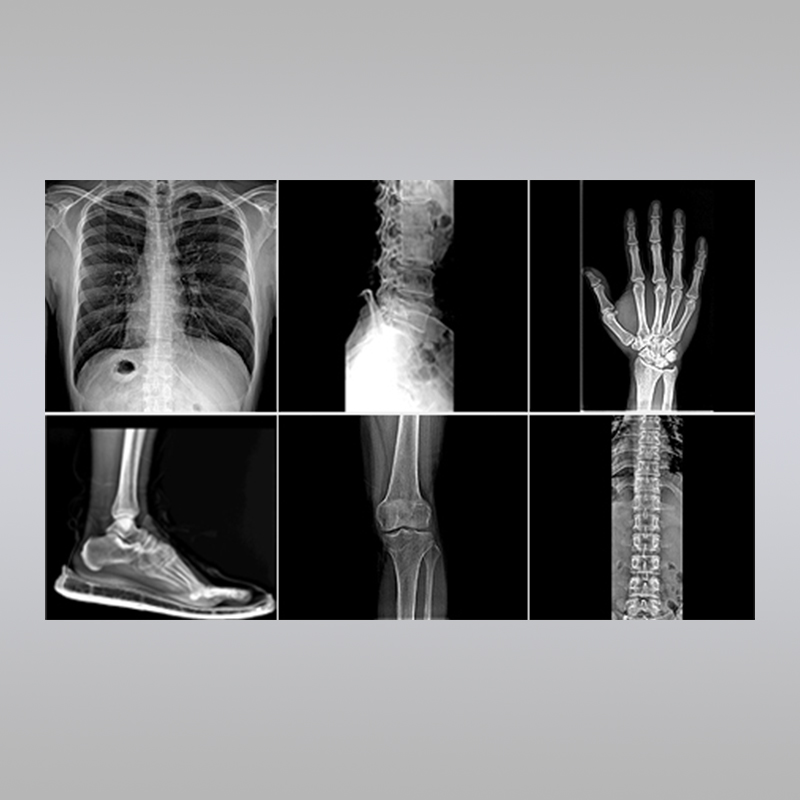

具有高分辨率和高对比度,能够清晰地显示各种组织和器官的细节,大大提高了病变的检出率。

可以通过调整窗宽窗位等参数,更好地观察不同组织的结构,为诊断提供更丰富的信息。

拥有强大的图像后处理功能,如放大、缩小、旋转、测量等,有助于医生更准确地分析病情。